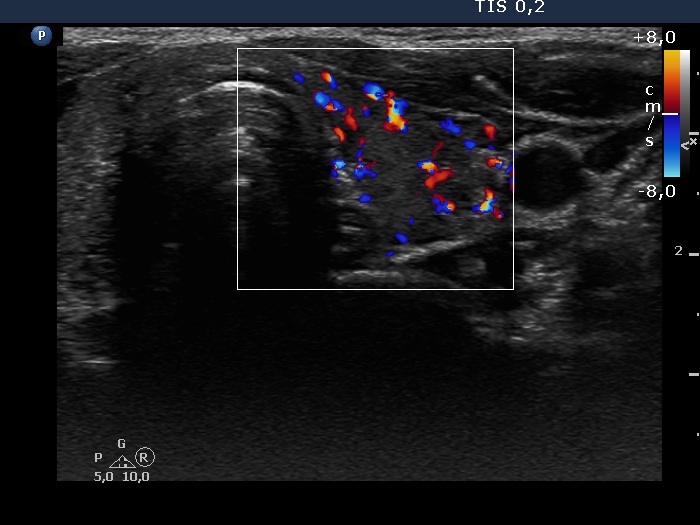

Consecutive patients with the final diagnosis of Hashimoto's thyroiditis - case 3 (1756) (ultrasonographic picture 6)

Left lobe, transverse scan, color Doppler mode. The vascularization is increased.